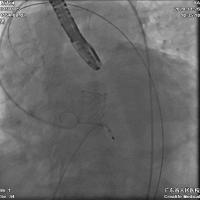

瓣膜植入后,即刻跨瓣压差几乎为零,无残余瓣周漏,顺利结束手术。

相较而言,Edwards Sapien 3球扩瓣的输送系统更细、柔韧性更佳,具有优异的可调弯特性,能够有效减少手术操作中对升主动脉的影响;在搭配一根相对柔软的导丝之后,该款瓣膜在整个手术过程中十分顺畅地完成了过弓、跨瓣、调整同轴性等操作,对于这样一例严重横位心的病例来说,这是极其难得可贵的。从术后即刻评估结果也可看到,瓣膜的释放位置与形态均令人满意,残余瓣周漏几乎为零,达到了非常好的手术效果。另外,由于瓣膜自身支撑力较好,Edwards Sapien 3球扩瓣在完成释放后始终维持着良好的圆形瓣膜结构,这一点也是其他自膨胀式瓣膜所无法企及的。过去,我们普遍认为应用球扩瓣治疗二叶式主动脉瓣狭窄患者的疗效不佳;然而,从现有的国外经验以及自身使用体验来看,球扩瓣反而可能为患者带来更多获益。